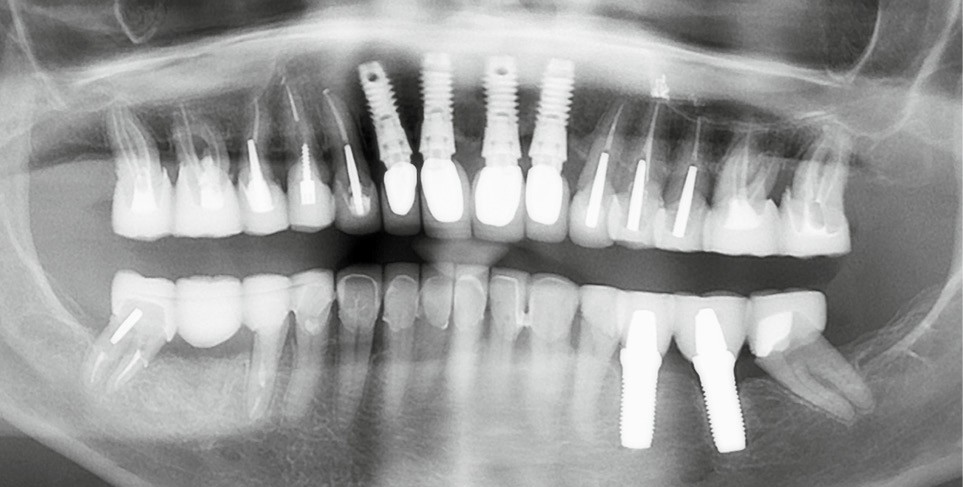

Une patiente ayant perdu ses incisives maxillaires à la suite d’un traumatisme quelques années auparavant, consulte en 2015 pour un inconfort occlusal persistant. Elle a été traitée par diverses gouttières occlusales, sans résultat notable. En 2017, une reconstruction globale est réalisée, toujours sans résolution de la plainte d’inconfort occlusal. Après avoir consulté de très nombreux praticiens et bénéficié de multiples traitements, en 2024 la patiente a perdu l’ensemble de ses dents ! En octobre 2025, après plusieurs prothèses globales sur implants, la plainte est toujours la même dans un contexte psycho-émotionnel de plus en plus difficile (fig. 1).